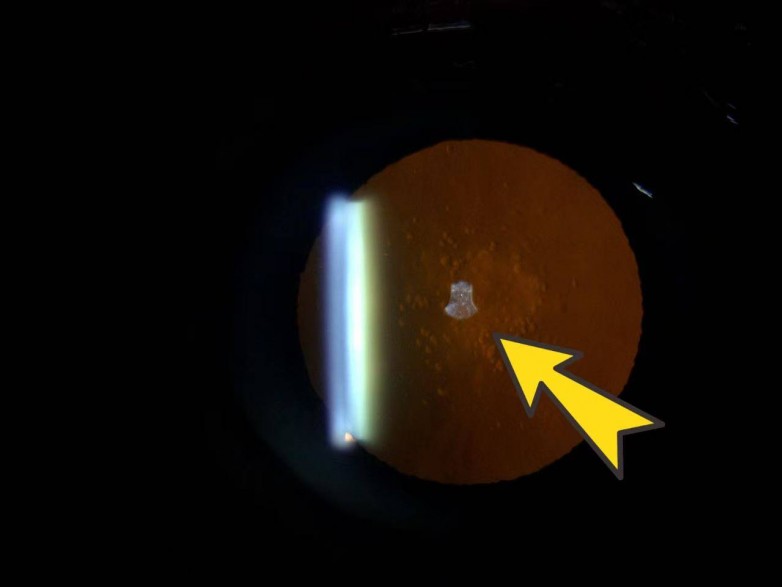

“检查显示,张女士的眼部条件原本符合近视手术的基本要求,但在细致排查时,我们发现她右眼的晶状体存在混浊情况,最终确诊为后囊下型白内障。”接诊医生表示,这样的结果意味着张女士暂时无法进行近视手术,这让满心期待的她倍感遗憾。更让医生关注的是,38岁患上白内障并不常见,属于相对年轻的病例,背后大概率存在特殊诱因。

晶状体后囊下混浊且位于视线中央,早期白内障视力已受影响,尤其白天强光下更明显